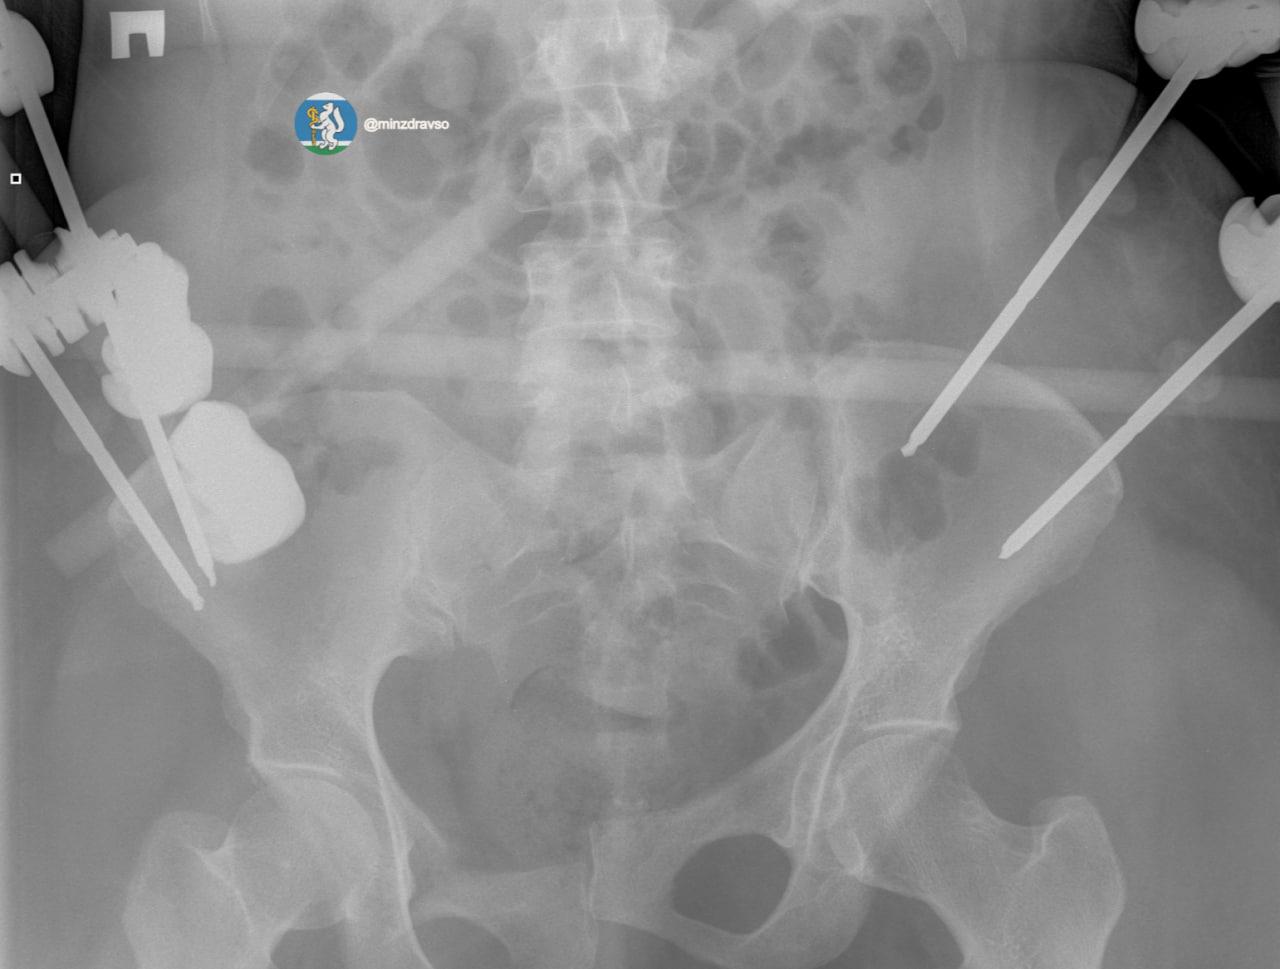

По данным министерства здравоохранения Свердловской области, благодаря вовремя прибывшей бригаде «скорой» удалось сохранить драгоценные минуты и доставить женщину в больницу, где в течение первых 15 минут были проведены все необходимые исследования. Врачи диагностировали тяжелую политравму, включающую закрытую черепно-мозговую травму, ушиб головного мозга, повреждение челюстно-лицевых костей, ребер, двусторонний пневмоторакс, оскольчатый перелом правой ключицы и раздробленные кости таза.

«Крайне тяжелое повреждение таза представляло высокий риск массивной кровопотери, поэтому борьба за жизнь пациентки началась с немедленной стабилизации ее состояния. Медики качественно скрепили отломки костей всех поврежденных сегментов костей и таза аппаратами внешней фиксации.   Профессионализм и опыт врачей, их высочайшая квалификация и плановое совершенствование экстренной медицинской помощи в Свердловской области подарили пациентке получить второй день рождения», — отметили в минздраве региона.

Аппараты внешней фиксации помогли пациентке минимизировали последствия травм, тем самым сохранив качество жизни. Сейчас женщина уже дома с семьей.